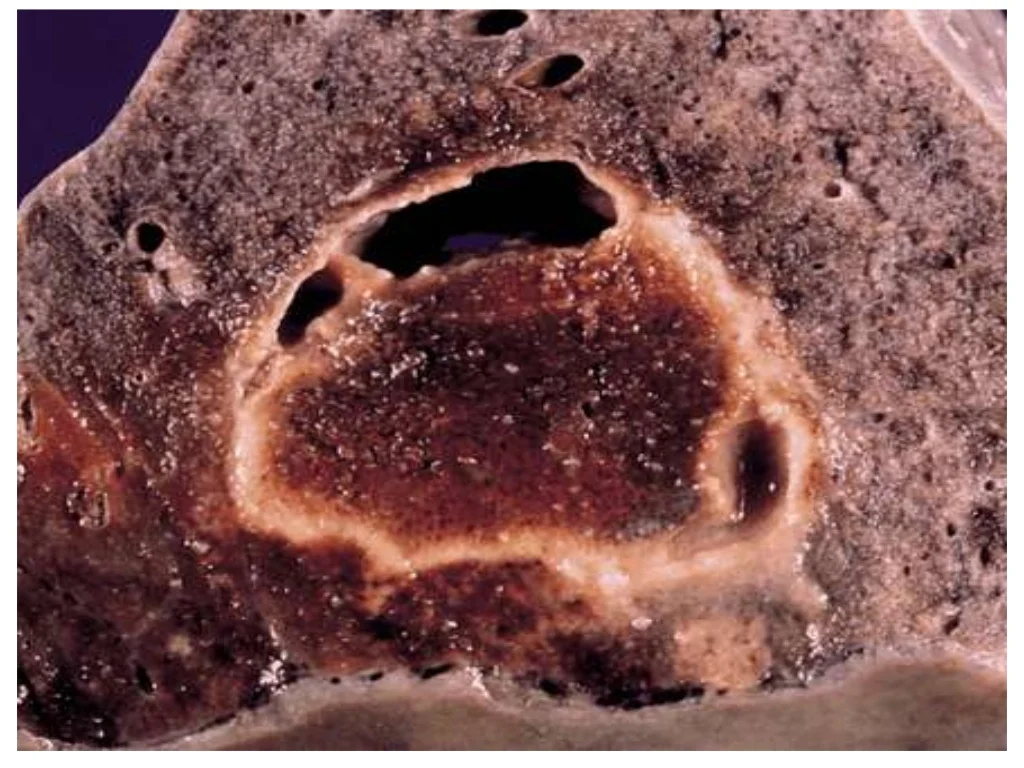

“Mereka menunjukkan kepada kami gambar paru-parunya. Jika dilihat secara langsung, paru-parunya terlihat seperti keju Swiss,” kata ayah Ian, Ron Pritchard, yang dikutip dari NY Post, Jumat (9/2/2024).

“Infeksi jamur Blastomycosis merusak paru-paru Ian hingga tidak bisa diperbaiki lagi,” tulis halaman tersebut.